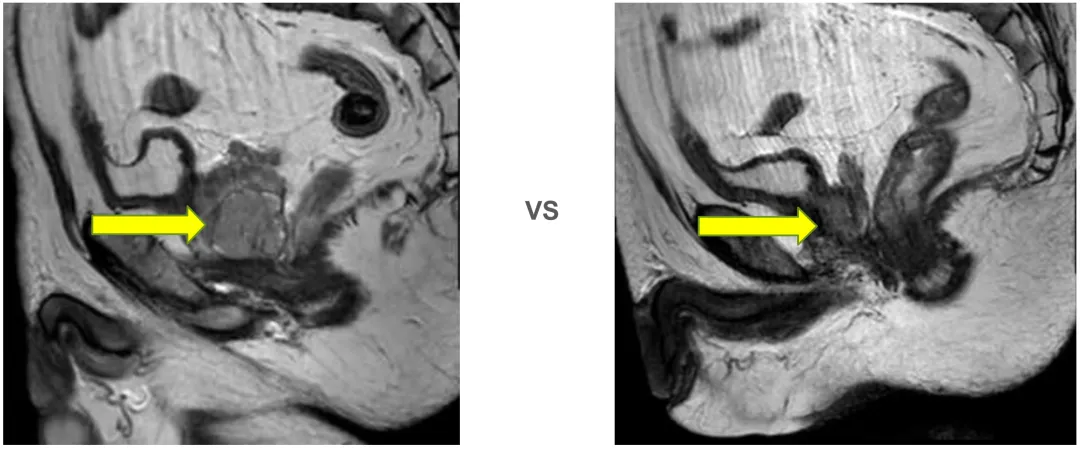

2025年9月12日 前列腺平扫+弥散(DWI)

(2024-11-28 vs 2025-9-12)

前列腺大小约为3.4cmx3.3cmx3.0cm,形态异常,右侧包膜欠光整,右侧周围带见结节状异常信号灶,T2WI低信号,T1WI低信号,DWI信号不高,边界欠清,长径约为0.9cm,左侧周围带信号不均匀减低,中央带及移行带信号不均。双侧精囊腺对称,充盈尚可。膀胱充盈可,其内未见异常信号灶。直肠因围脂肪间隙未见异常。扫描野内未见明显肿大淋巴结,扫描野内右侧股骨头及髋臼内见斑片状异常信号灶。

1. 结合病史,考虑前列腺右侧周围带肿瘤治疗后改变。

2. 右侧股骨头及髋臼异常信号灶,考虑退行性变可能。

前述改变与前片(2025-06)比较未见明显变化,建议隔期复查。